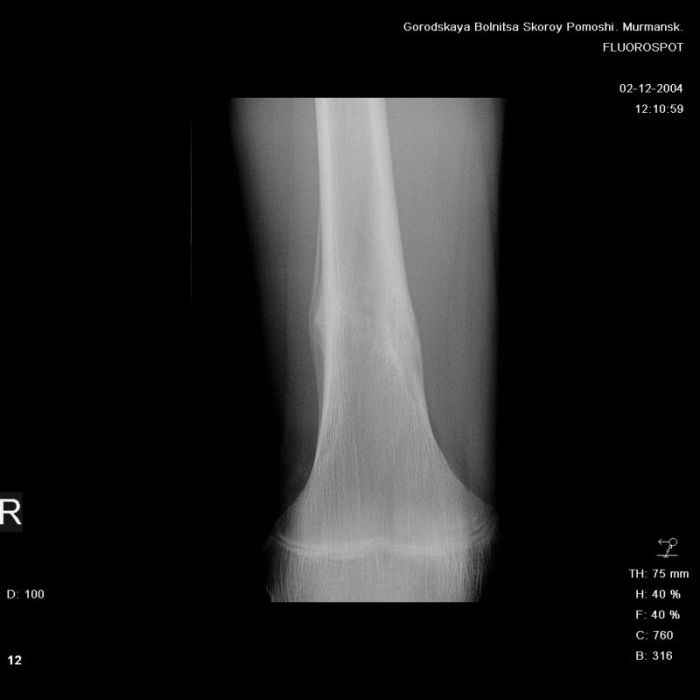

Анамнез практически никакой: в следствие травмы (растяжение связок коленного сустава) от 07.11.2004 выполнены Rg-граммы в травмпункте и обнаружено опухолевидное образование. Первичные Rg-граммы я не публикую, так как они заметно худшего качества, да и динамики за прошедшие три недели не отражают. Болевой синдром купирован в течение трёх дней. В настоящий момент мальчика ничего не беспокоит. Ходьба не нарушена, опухоль пальпируется с трудом по задней поверхности в н\3 правого бедра, пальпация безболезненна, объем движений в суставах правой нижней конечности полный и симметричный. Кожа над опухолью не изменена.В нашей клинике проведено дополнительное обследование: общие анализы крови и мочи, биохимия крови без особенностей. Выполнены Rg-граммы на цифровом Siemens обычные и продольные томограммы срезами 3-5 мм, а также компьютерная томография поперечными срезами по 5 мм. Прошу обратить внимание, что на приведённых томограммах видны две полости 10х15 мм и 15х60 мм. Также имеются два опухолевидных образований наслаивающихся друг на друга: уплощённое и вытянутое 10х100 мм и элипсовидной формы 15х30 мм. Это хорошо заметно на фото a_1.jpg c_1.jpg и d_1.jpg. Плотность внутри полостей 125% от плотности костномозгового канала, плотность наружного опухолевидного образования 55% от плотности кортикального слоя. Также отмечается линия перелома по центру наружного опухолевидного образования.Исходя из полученных данных мнения в плане диагноза несколько разделились от 1)сочетания кортикальной фиброзной дисплазии и латентно протекавшего маршевого перелома н\3 правого бедра до 2)остеосаркомы. В отношении первого варианта не сходится отсутствие клиники при переломе такой крупной кости как бедро, второй вариант вообще оставлю без комментария, ибо некомпетентен. Хотелось бы услышать мнения коллег, с удовольствием ознакомлюсь с любыми предположениями и замечаниями.С уважением, Александр Е. КлоковОтделение детской ортопедии и травматологииБСМП г. Мурманска.